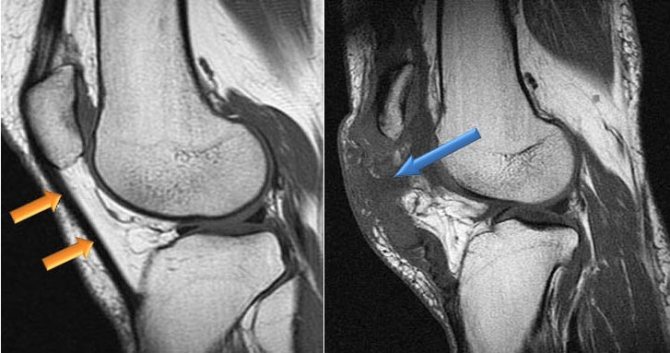

Иногда для того, чтобы исключить другие причины болей в коленном суставе, например, боль при повреждениях и разрывах менисков, особенно передних отделов, может быть полезной магнитно-резонансная томография (МРТ), которая позволяет увидеть мягкие ткани (мениски, связки, сухожилия, хрящ, мышцы и т.д.). При тендините связки надколенника на МРТ часто обнаруживают усиление сигнала в области нижнего полюса надколенника и в самой связке, однако интенсивность сигнала не всегда соответствует выраженности симптомов. В ряде случаев при тендиниите на МРТ связка может быть утолщена.

Магнитно резонансная томограмма при тендините надколенника.

Благодаря поверхностному расположению, связка надколенника доступна для УЗИ. Опытный врач может обнаружить утолщение связки, дегенеративные изменения, а также частичные и полные разрывы. В стадии регенерации на УЗИ с допплеровскими датчиками может быть зарегистрировано усиление кровотока.